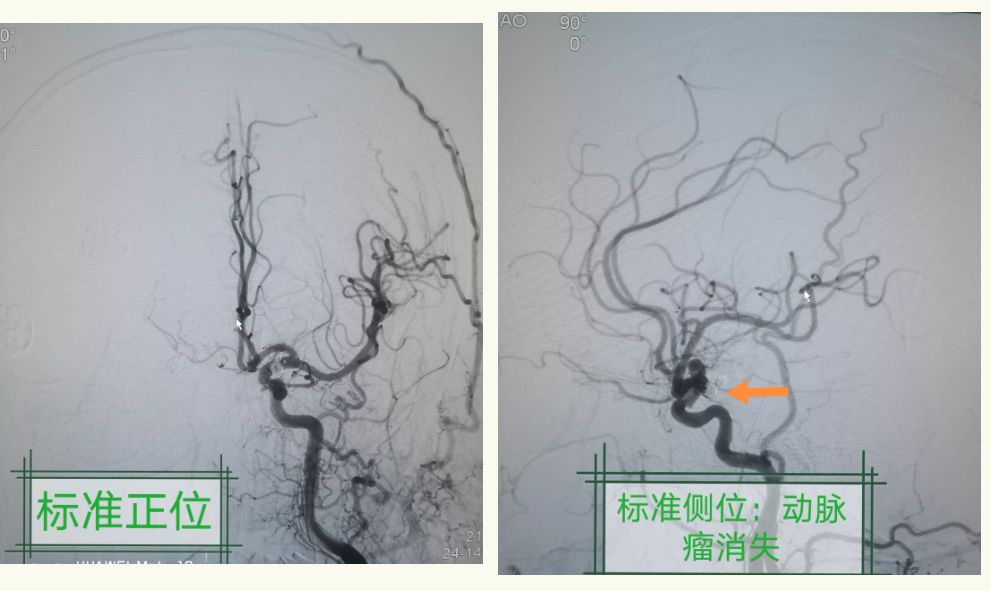

神经外科王宝庆副主任与患者家属进行了多次深入的病情沟通,征得患者家属的信任和同意,进一步行脑血管造影(DSA)检查明确诊断,DSA检查结果显示:左侧颈内动脉交通段动脉瘤。动脉瘤形态不规则,呈现分叶状,由此可见,动脉瘤破裂出血是本次发病的罪魁祸首。

脑动脉瘤的危害极大,会引起脑积水、脑出血并发症,第二次破裂出血的死亡率高达50%以上,如果病症进一步加重,患者随时有死亡的危险。12月15日晚,神经外科为患者急诊行动脉瘤支架辅助弹簧圈栓塞术。手术进行了三个小时,一切顺利。期间刘增良副院长一直陪伴到手术结束,为手术团队提供了强大的支持和保障。

术中造影:图中可以看到动脉瘤中的弹簧圈和载瘤动脉内的支架。

术后造影:证实动脉瘤栓塞满意,载瘤动脉通畅,颅内血管均通畅,血供良好。